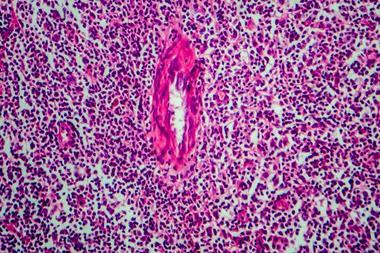

The innovation is set to change how eligible bladder cancer patients in the US are treated who are unresponsive to traditional therapy.

Recent authorisation of Inlexzo ™ (gemcitabine intravesical system) by the US Food and Drug Administration (FDA) offers certain patients with Bacillus Calmette-Guérin (BCG)-unresponsive non-muscle invasive bladder cancer (NMIBC) a novel treatment alternative.

It is indicated for NMIBC patients with carcinoma in situ (CIS), with or without papillary tumours, and for individuals who have limited options prior to possible bladder removal.

Clinical data demonstrating the drug’s high response rate supported the FDA’s decision. In the SunRISe-1 Phase IIb study, 82 percent of patients attained complete response without the need for reinduction, according to Johnson & Johnson. Of these patients, 51 percent sustained this response for at least 12 months.